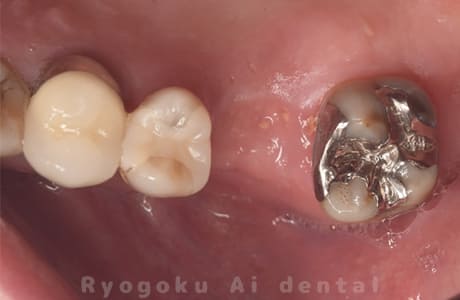

Case12

- 左下7番歯牙破折

-

- 治療内容

- インプラント治療

- 治療費用

- 約600,000円

左下の奥歯が痛いとのことでご来院された患者様です。歯が完全に割れており、保存が不可能であったため、抜歯を行い、その際に骨に変わるお薬を入れ、十分な治癒を待ってからインプラント治療を行いました。経過良好で、大変満足されました。

<リスク・副作用>

治療後、痛みや違和感、出血、腫れなどが出る事があります。喫煙者、糖尿病などの方の場合、歯が生着しない場合があります。